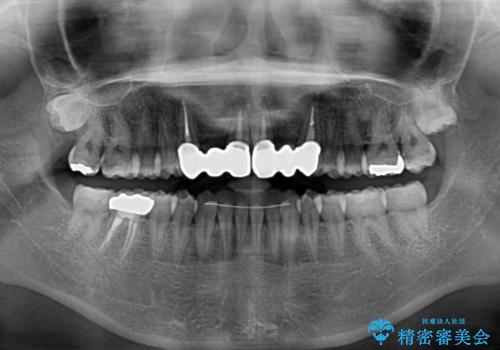

矯正治療後に前歯をセラミックブリッジに、奥の銀歯はセラミックインレーやPGAインレー(ゴールドインレー)にて補綴・修復治療を行うこととしました。

矯正治療により下顎前歯を整列させたため、上顎前歯のセラミックブリッジを補綴することで口元を少し下げることができました。

ヒトの目線がいつも口元に向けられているように感じることがなくなり、患者様には大変満足していただきました。